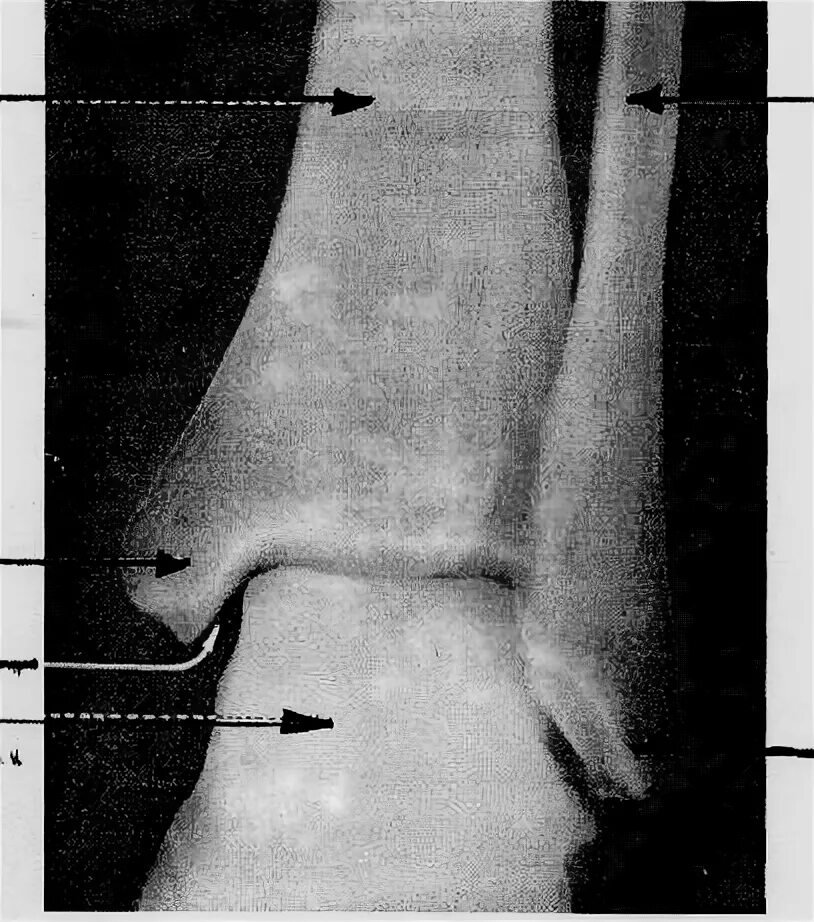

Суставная щель 3 3 мм